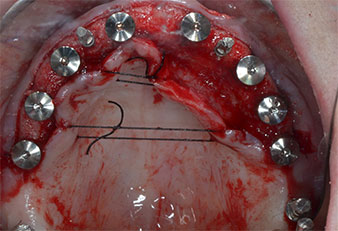

Поради сравнително твърдата кост (D2) в тази област, 10-милиметровото имплантно ложе в позиции 11 и 21 беше завършено с ротационен дрил с диаметър 4 mm в комбинация с W&H хирургичен обратен наконечник WS-75 L, W&H имплантологичен мотор Implantmed и опционалния W&H Osstell ISQ модул. За разлика от това, благодарение на меката кост, дисталните зони се подготвят до окончателен диаметър 3 mm, използвайки накрайник за Piezomed I3P. Имплантите най-накрая са поставени трансгингивално, за да остеоинтегрират за три месеца (Фиг. 6-10). Съществуващата протеза се фиксира на четирите временни импланта (Фиг. 8).

10-милиметров имплант на нивото на меките тъкани

Фиг. 6 10-милиметров имплант на нивото на меките тъкани е поставен на позиция 21. Имплантът в позиция 11 и трите леви дистални 4-милиметрови импланта са вече на мястото си.

Стабилност на импланта

Фиг. 7 Стабилността на импланта е установена със SmartPeg и W&H Osstell ISQ модул. Стойностите са в средния към високия диапазон с минимум ISQ 69.

Временни импланти

Фиг. 8 След фиксиране на гингиво оформителите временните импланти се поставят в позиции 18, 12, 22 и 28.